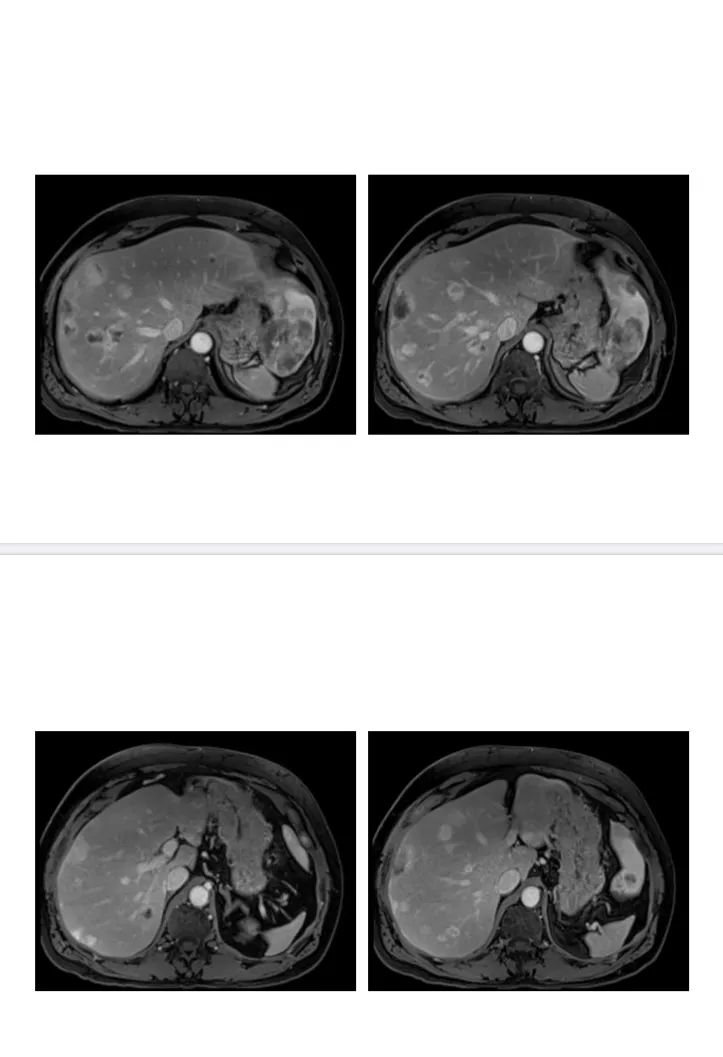

肝脏多发结节及肿块,平扫等 延迟等,考虑恶性程度不高病变。1t2高首先需要考虑血管源性肿瘤,血管瘤,周围环状强化,不太符合,ehe病灶大部分征象符合,有一病灶可见棒棒糖征,一般中心有坏死,本例没有,也未见明显包膜收缩,部分病灶靠中心分布,血管肉瘤,一般中心强化,有坏死。2转移瘤,神经内分泌癌,一般也有坏死。3炎性肉芽肿或炎性假瘤,影像表现符合,需要重点考虑。建议查看白细胞及CRP,综合考虑炎性假瘤或肉芽肿>ehe>神经内分泌肿瘤。

肝多发病灶,包膜下分布为主,T2WI信号比较高,富血供,向心性充填,符合血源性肿瘤。EHE? 医学百科网 | YxBaike.Com

肝脏多发包膜下肿块,渐进性强化填充,棒棒糖征,包膜回缩,常规考虑EHE,鉴别转移瘤!

老年女性,肝实质密度减低,肝内多发结节灶,包膜下分布为主,渐进性强化,部分见棒棒糖,倾向EHE,鉴别血管肉瘤及炎性病变。

肝脏多发肿块,部分位于包膜下,渐进性强化填充,部门呈环状强化,部分可见棒棒糖征,部分包膜回缩,首先考虑EHE,鉴别转移瘤(病史)。 医学百科网 | YxBaike.Com

肝脏多结节和团块,呈长1长T2,增强动脉期部份结节边缘强化,门脉期诸病灶均显示明显强化,以边缘强化为主,延迟期造影向病变内进一步充填。脾脏内也可见多发大小不等的团块,增强不均匀强化。考虑血管源性恶性肿瘤。